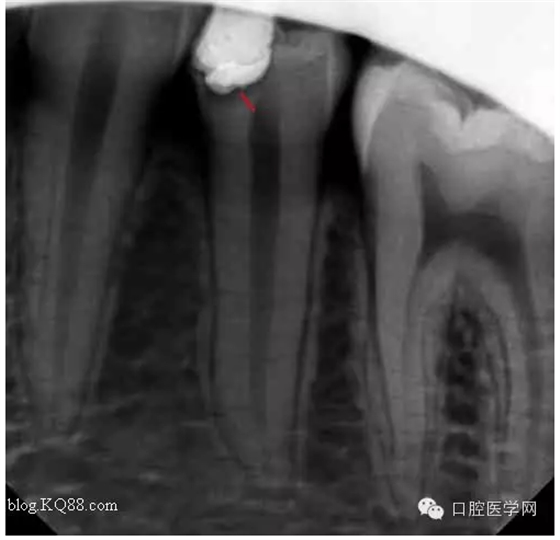

一月后復(fù)查:高聳的髓角變鈍,形成約0.5mm修復(fù)性牙本質(zhì)?;佳罒o(wú)癥狀。牙髓活力測(cè)試同對(duì)照牙。

兩月后復(fù)查:高聳的髓角變的更鈍。遠(yuǎn)中髓壁形成較厚的修復(fù)性牙本質(zhì)。溫度測(cè)試同對(duì)照牙。

三個(gè)月后復(fù)查:高聳的髓角消失。形成約1mm的修復(fù)性牙本質(zhì)。患牙無(wú)癥狀,溫度測(cè)試同對(duì)照牙。此時(shí)修復(fù)性牙本質(zhì)的形成已趨于穩(wěn)定。每次復(fù)查的溫度測(cè)試是判斷牙髓活力,有時(shí)雖然沒(méi)有臨床癥狀,但牙髓受到慢性刺激會(huì)無(wú)痛性漸進(jìn)性壞死。導(dǎo)致保存活髓失敗。

所以每次復(fù)查的溫度測(cè)試必不可少的。